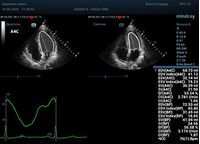

Что могут предложить современные приборы? Приборы нашего времени являются мощными вычислительными машинами, способными обрабатывать полученную информацию даже без помощи человека. Система автоматического вычисления фракции выброса – AUTO EF на

приборах серии Resona компании Mindray сделает все за вас. За пару секунд прибор сам отыщет нужную фазу сердечного цикла и произведёт измерение и расчеты, а также покажет график изменения объема в сердечном цикле. От Вас требуется только получить качественное 4С и 2С сечение. Впрочем, прибор всегда оставляет возможность коррекции, если доктор имеет свое мнение на расположение точек планиметрии или момента измерения по ЭКГ каналу.